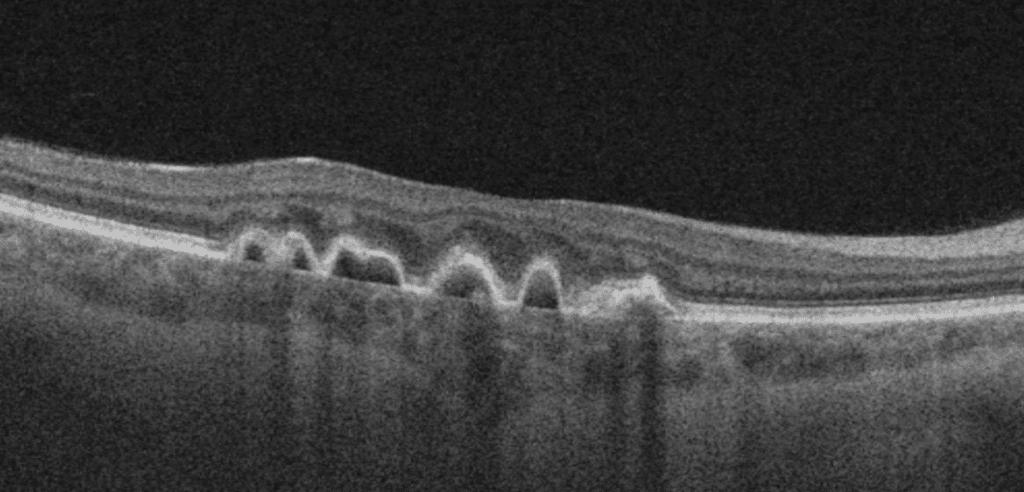

On examination, she had a best corrected visual acuity of 20/20 vision in both eyes. Intraocular pressures were normal and the anterior segment examination was unremarkable. Posterior examination revealed retinal pigment epithelium (RPE) mottling and pigment epithelial detachments (PED) in the macular region as well as nasally in both eyes. Fundus findings were symmetric in both eyes (see Figure A-D). Optos ultra-widefield imaging revealed macular RPE mottling with PEDs in the macula and nasally (see Figure A). Ultra-widefield fundus autofluorescence demonstrated hypoautofluorescent areas with hyperautofluorescent borders in the macula with hyperautoflourescent spots nasally (see Figure B). Macular optical coherence tomography (OCT) scans of both eyes showed PEDs with Bruch’s membrane thickening along with sub-RPE drusen-like deposit (see Figure C).